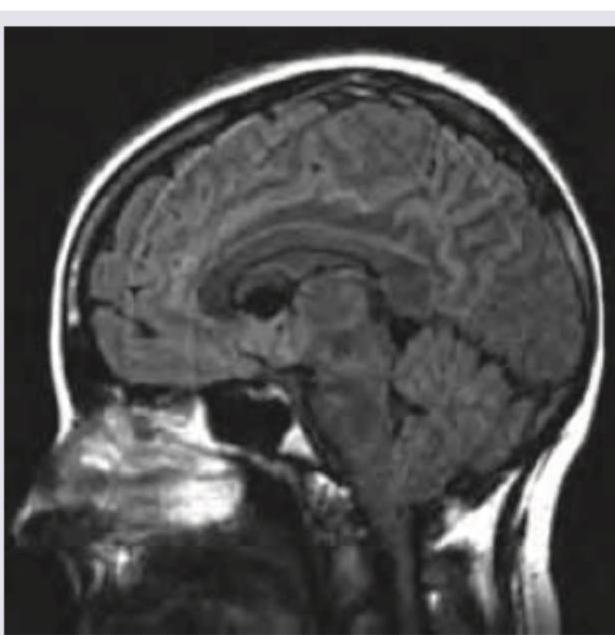

Question 17: All are true about CNS malformation shown below except:

- A. Large posterior fossa (Correct Answer)

- B. Herniation of cerebellar tonsil

- C. Herniation of cerebellar vermis

- D. Association with myelomeningocele

Explanation: ***Large posterior fossa*** - The image shown, consistent with a **Chiari II malformation**, typically features a **small posterior fossa**, not a large one. - A small posterior fossa contributes to the crowding and herniation of cerebellar structures through the foramen magnum. *Herniation of cerebellar tonsil* - **Chiari II malformation** is characterized by the **downward displacement of the cerebellar tonsils** through the foramen magnum. - This herniation can lead to obstruction of CSF flow and associated neurological symptoms. *Herniation of cerebellar vermis* - The image suggests a **Chiari II malformation**, which involves the **caudal displacement of the cerebellar vermis** and fourth ventricle into the spinal canal. - This is a hallmark feature distinguishing it from other Chiari malformations. *Association with myelomeningocele* - **Chiari II malformation** has a strong and consistent association with **myelomeningocele**, a severe form of spina bifida. - Most patients with myelomeningocele will also have a Chiari II malformation, indicating a common developmental origin.